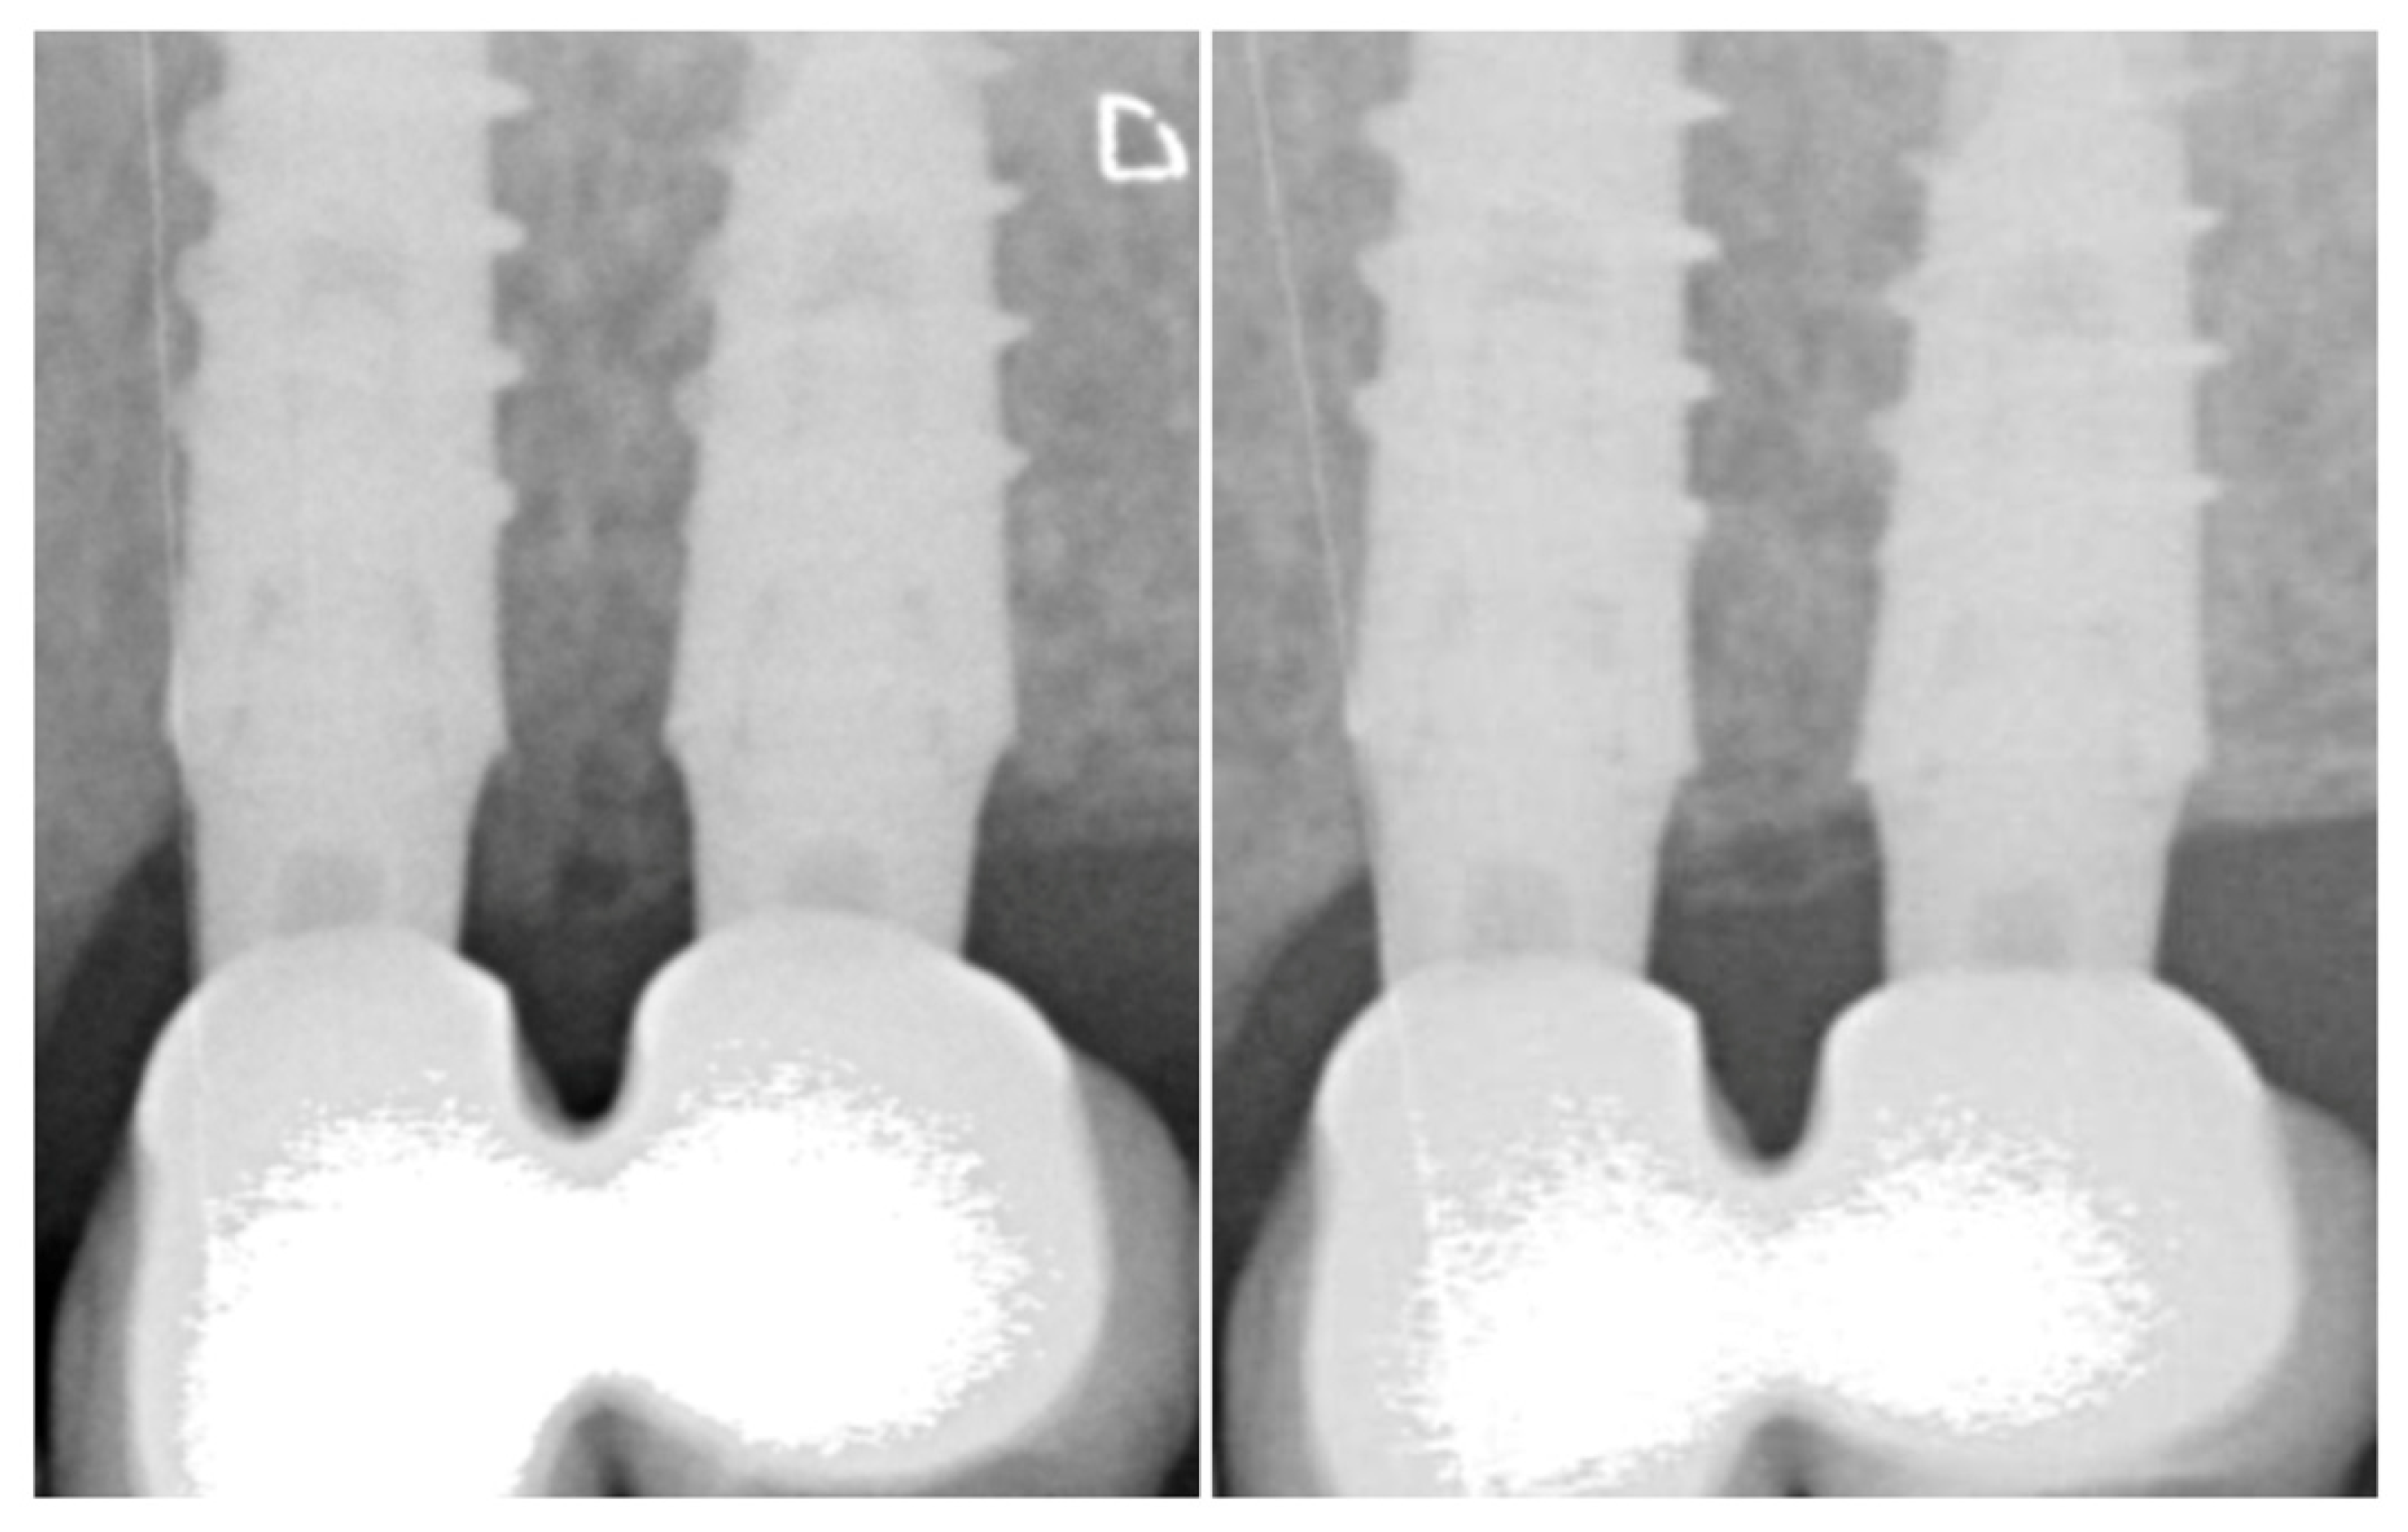

2.3. Radiologic Marginal Bone Level Evaluation

| Time-point | Mesial MBL | Distal MBL | Mean MBL | Delta MBL | p-value |

|---|---|---|---|---|---|

| Mean MBL in function by year, mm (per implant analysis) and statistical significance of time-effect. | |||||

| Overall | |||||

| Baseline | 1.47 ± 0.87 | 1.30 ± 1.01 | 1.39 ± 0.91 | ||

| 1-year | 1.28 ± 0.98 | 1.04 ± 0.92 | 1.16 ± 0.91 | −0.18 ± 0.72 | 0.01 |